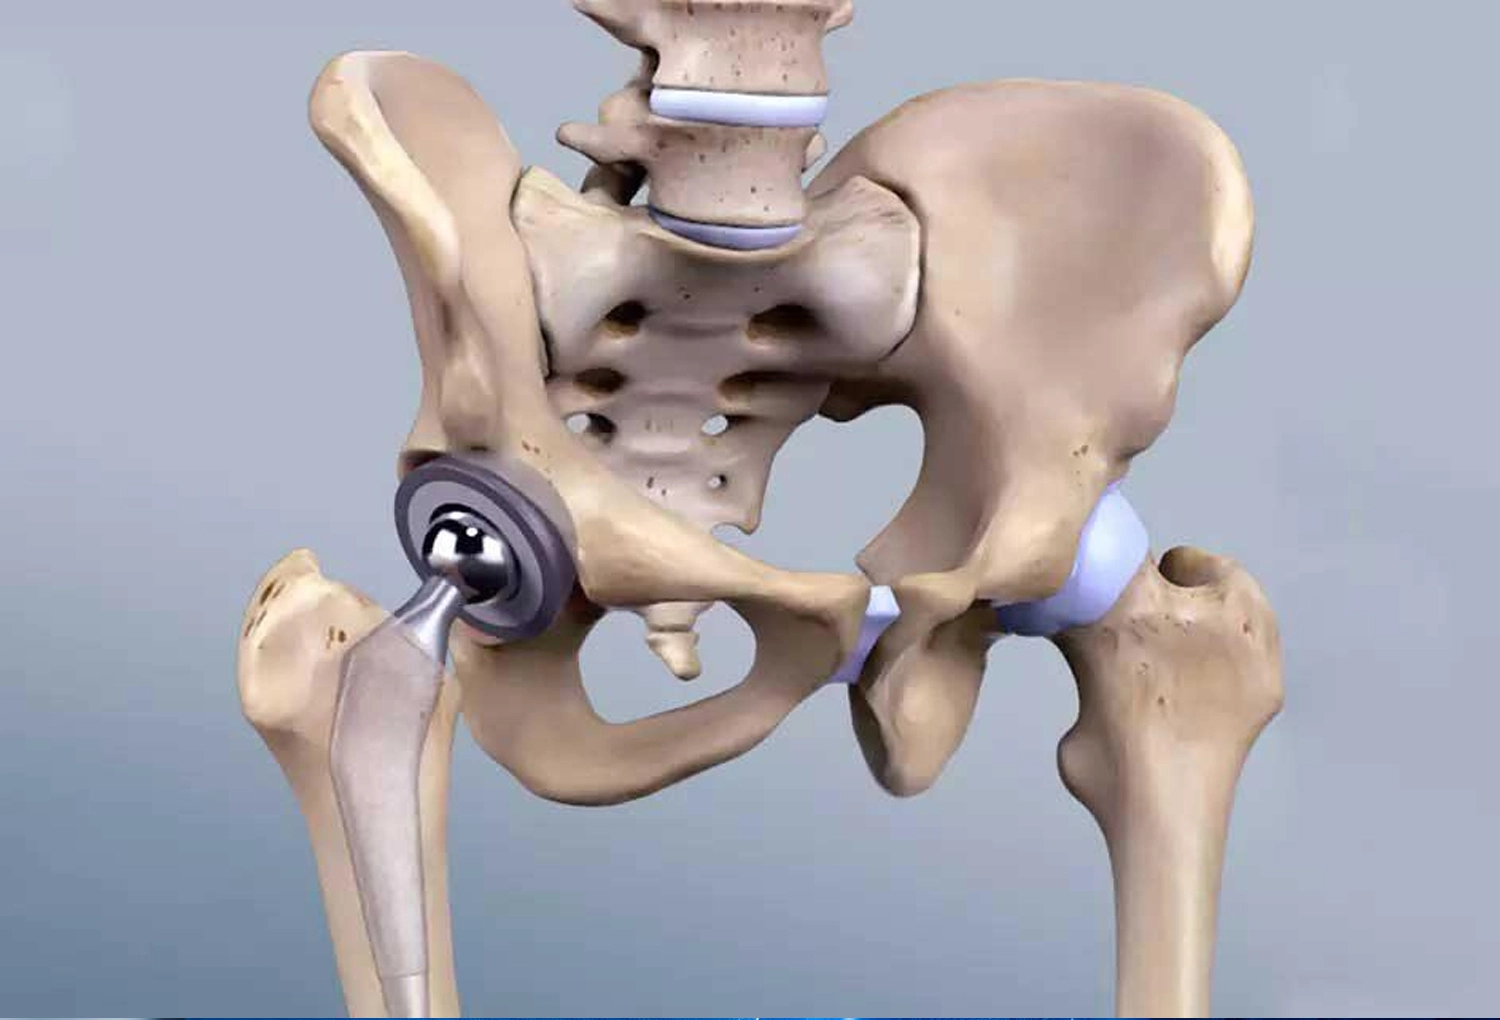

Soins médicaux avancés par des spécialistes pour diagnostiquer et traiter diverses pathologies avec expertise, sécurité et suivi personnalisé, idéals pour le tourisme médical.

MÉDECINES SPÉCIALISÉES

La Cardiologie est une spécialité médicale dédiée au diagnostic, au traitement et à la prévention des maladies du cœur et du système vasculaire

La neurochirurgie est une spécialité médicale dédiée au traitement chirurgical des maladies du cerveau